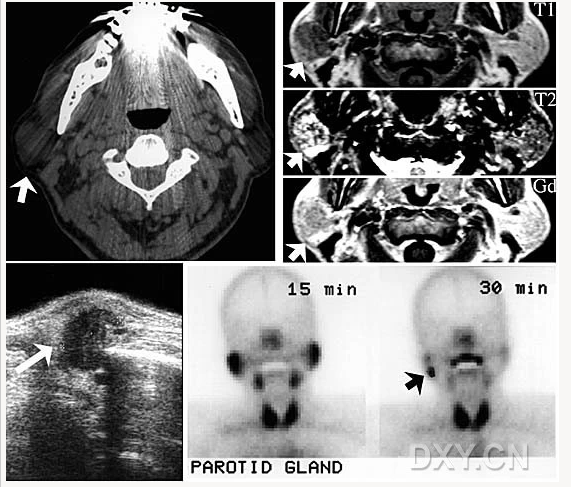

舍格倫綜合征

腺淋巴瘤[沃辛瘤